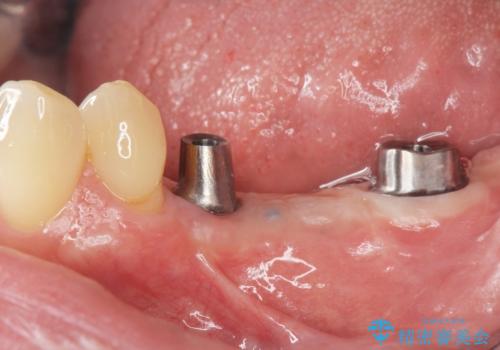

臼歯部インプラント補綴

- 奥歯で物が噛めず、食事が楽しめなくなってしまった。しっかり噛んで食事ができるようになりたいと来院されました。

予後の不安な小臼歯と、すでに大臼歯は2本喪失した状態で咀嚼機能に大きく問題がある状態です。

グラつきのある小臼歯は、抜歯を行い2本のインプラントを埋入することでしっかりと咬合機能を回復できる治療を計画します。